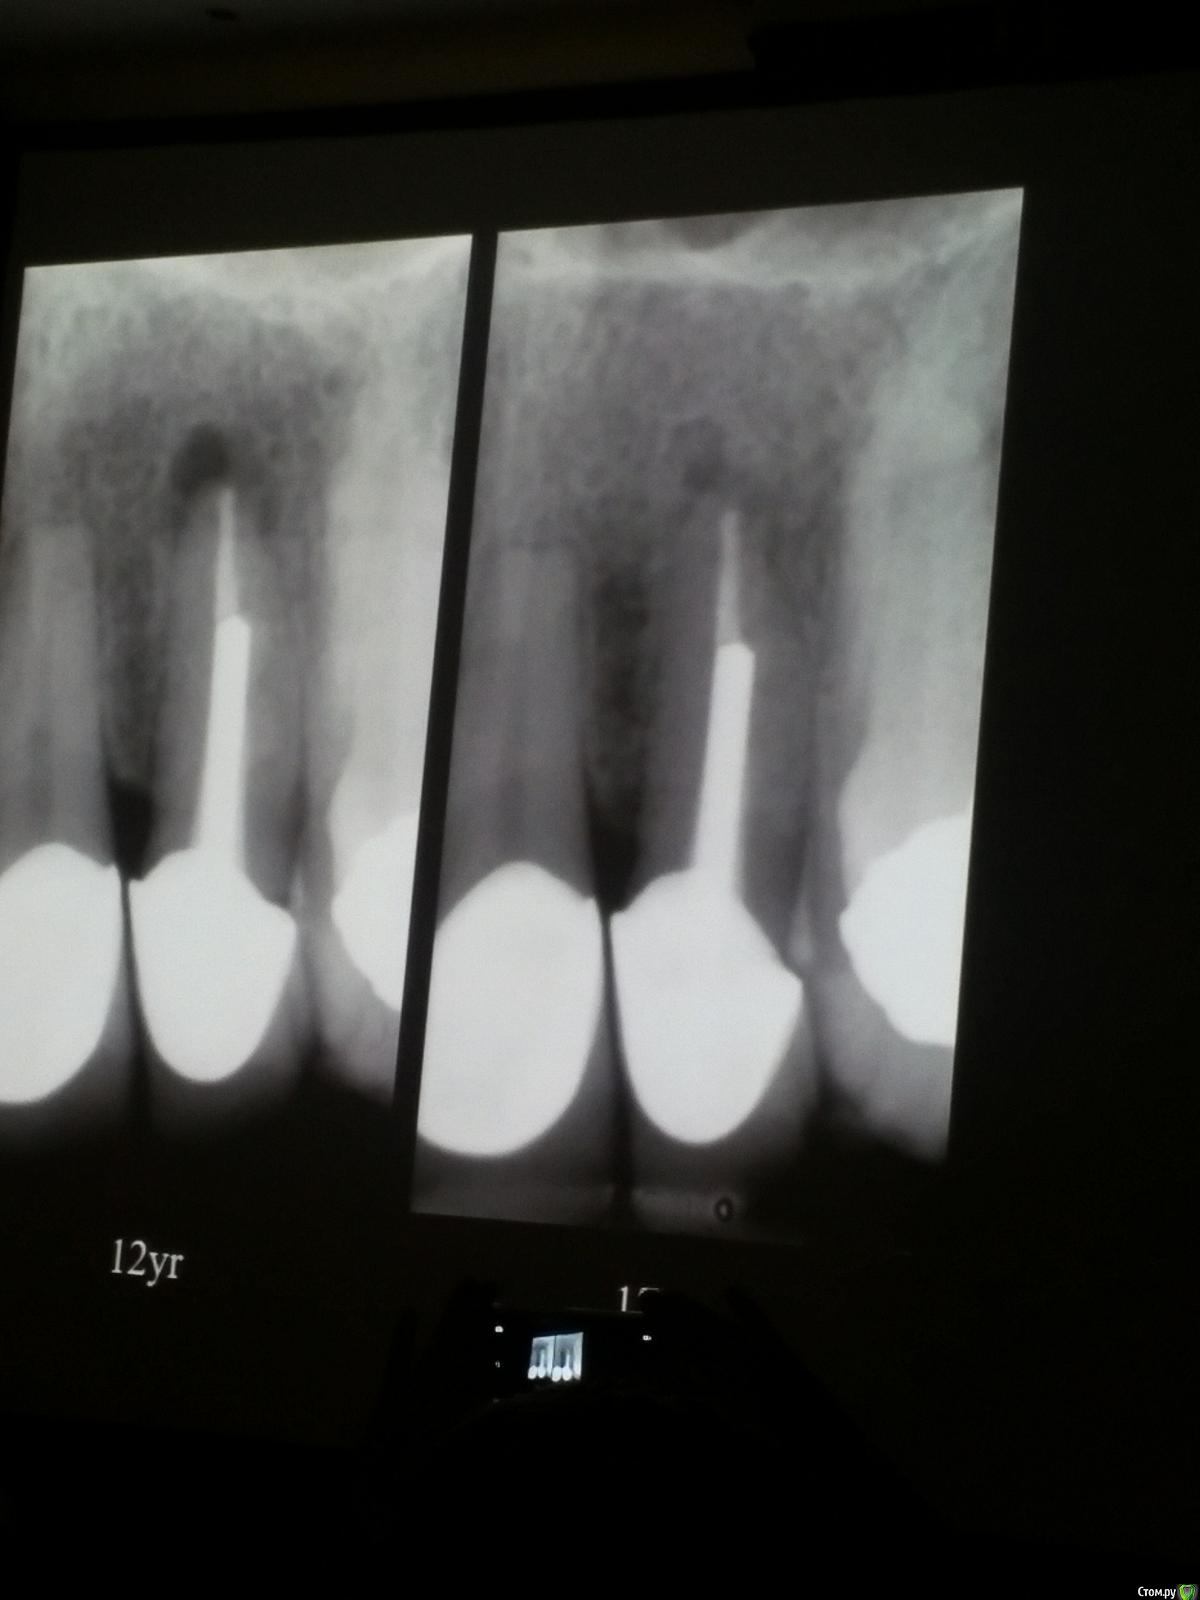

Популярный пост Kolchanov Опубликовано 11 марта, 2017 Популярный пост Поделиться Опубликовано 11 марта, 2017 (изменено) Товарищи, скажу я вам...........Вкратце. Может я где-то что-то и приврал, надеюсь, кто еще был, поправят. Честно говоря немного прибалдел от уровня Доктора. Очень, очень высоко! Приедет еще раз, пойду еще. 1) Фиссуры зондирует острым зондом и выпиливает все дотла. По факту у него уже пломбы, а не герметизация.2) Bite-wing у первичных пациентов всегда.3) Если кариес диагносцирован, то лечить его, пофиг какой он там. Эмали, дентина…4) Препарирует до твердого (или до вскрытия J ). CAD, СID… в топку. Кариес маркером не пользуется, проверяет острым зондом/экскаватором. Вычищает все дотла. Считает, что даже небольшое количество бактерий в дентине под пломбой вызывают хроническое воспаление в пульпе. С его слов у него на контроле где-то 500 вскрытий, не удивительно при таком подходе к очистке.5) Тщательная изоляция. Коффер порвался – меняет. Большое значение герметичности реставрации. под замену6) Критерии обратимости и необратимости.Гистологически, обратимый тот, что без абсцессов в пульпе, но клинически это понять нельзя, только предположить.Здесь был бы обратимый, если бы не удалил. Нет микробов в пульпе. Линия - граница обработки.Покрытие 27 лет назад. Dycal, СИЦ, композит. От дайкала одно воспоминание.7) Вскрылись. Размер перфорации, возраст и прочее не играют роли, важно только состояние пульпы, т.е. диагноз.Примеры перфораций.8) Кровотечение останавливает стерильным ватным шариком. Если останавливается, то покрытие, если нет, то пульпотомия или пульпэктомия.9) Использует гидроокись кальция (порошок), перекрывает Dycal или СИЦ. Потом восстановление Нередко под IRM, потом все убирает (через пару-тройку месяцев) и смотрит, что получилось. Порой приходится повторять! Использует и МТА, его тоже убирает.10) Наблюдение 6мес, 1 год, 2…. Все может провалиться и через месяц и через 24 года.Примеры проваловНиже - 24 года спустя появилась дуля. 11) Неравномерная облитерация полости зуба на RG (после покрытия) – признак текущего хронического воспаления, где-то остались микробы. Рекомендует эндо.12) Мостик который образуется – это не дентин! И одонтобласты не регенерируют и новые не образуются. Что это такое он и сам не знает, но раз это твердые ткани, то и наплевать.Вот фиолетовое это дентинные опилки вмурованные в розовую ткань бог знает кем сформированную.13) Пульпотомия в зубах с несформированной верхушкой и в сформированных, при подозрении на частичное поражение коронковой пульпы. Иссекается стерильным алмазным бором часть пульпы, гидроокись, временная пломба на 90 дней, после повторное раскрытие, оценка результата, восстановление в случае формирования твердых тканей. Гипохлоритом можно мыть, можно не мыть, если мыть, то 0,5-1%.14) В апикальной части пульпа чаще витальна, чем нет.15) Периапикальные поражения возникают по причине поступления токсинов микробов с током крови, а не самих бактерий.16) За апикальные расширения в полностью некротических случаях. Надо механически отодрать биопленку и срезать инфицированный дентин. На ирриганты надежды мало.17) Биопленка на поверхности в 6% случаев.Синенькие пид@расы18) Обработку проводить нежно, краун-даун. Чередовать с H-файлом, чтобы посмотреть докуда распространяется некроз.19) Патенси в витальных кейсах не колоть, сохранять витальную пульпу в констрикции!Формирование еще большего сужения в констрикции за счет сохранения витальной пульпы. Изменено 11 марта, 2017 пользователем Kolchanov 31 Ссылка на комментарий

Популярный пост Kolchanov Опубликовано 12 марта, 2017 Автор Популярный пост Поделиться Опубликовано 12 марта, 2017 Второй день.1) Дезинфекция зуба и раббер дама перед работой. Вначале установка системы, потом протирка тампоном 30% перекиси, потом протирка всего йодинолом. Потом преп, потом повторение и только потом доступ к к/к. Все старые реставрации надо убрать, кариес убрать, противник лечения через коронку.2) Гидроокись на неделю. Замешивает на стерильном физрастворе. При необходимости повторяет. Т.е. в случае сохранения свища, симптоматики, экссудации, запаха. Если свищ не исчезает после трех смен временных вложений, то хирургия.3) Пломбирует латеральной компакцией. Лучше контроль длины обтурации.4) Высушивание канала стерильными штифтами, на рабочую длину минус 1мм. После высушивания штифт оставляется на 60с. в канале и должен выйти сухим.5) Определение рабочей длины. Витальные случаи. АЛ должен три раза дать одну и ту же картинку в определенной точке + проверка RG. Девитальные случаи. На АЛ полагаться сложно, т.к. из-за наличия резорбции констрикции может врать, больше ориентируется на RG.6) Использует ЦОЭ силеры. Резорбируются при незначительном выведении. Резорбируются в канале, позволяя закрыть апекс цементоподобной тканью. Вот так вот.Случаи исчезновения силера, как за пределами канала так и в канале7) Выведение материала (не важно какого) в большом объеме способно вызвать защитную реакцию тканей. Которая должна пройти спустя некоторое время. (иногда это будет 25 лет J Случай 1ый. Студенты наломали инструментов. Периодонтит на RG через год. Резекция и гистология. Бактерий не обнаружил. Да, маленькое замечание. Каждый препарат дает 500-600 срезов. И ищет он на всех. Объем работы, конечно….Случай 2й. Его собственный. Периапикальное поражение, обнаруженное на реколле через 10 лет зажило еще через 15.8) «Функционирующий зуб» считает результатом неприемлемым. Осталась инфекция с которой надо что-то делать. То, что бактерий можно замуровать в дентинных трубочках и под пломбировочным материалом, считает неправильным. Продукты метаболизма один фиг будут просачиваться и могут поддерживать реакцию воспалительную.Случай. Синее – маленькая кучка микробов, предположительно, препятствовавших заживлению очага.9) Биопленка на поверхности корня может принимать вид кальцификатов (камней) и тут уже только хирургия в помощь. При длительном существовании свищевого хода, например.Черное - это камни вокруг апикального отверстия. И гистология их с кучей синих микробов.Здесь камни на фуркации и отсутствие заживления и свищ даже после ретроградной обработки и пломбировки.А здесь вообще чертова уйма камней. И зацените разветвление канала в этом боковом резце (последнее фото препарата). 10) Реваскуляризация.В некротических случаях дентина не образуется, т.к. одонтобластов нет и не будет новых. Образуется та самая бог знает какая ткань, которая даже и с корнем не связана может быть. Суть здоровый дентикль-петрификат. А в витальных это не реваскуляризация, а обычное формирование корня. Так что нечего тут.11) Трещины дентина.Советует расшивать, братья и сестры. Без фанатизма, если нет симптоматики, но, по возможности максимально. Если есть симптоматика, то там уже по обстоятельствам. Чертова уйма микробов там и ползет, ползет к пульпе. Надеюсь, что еще раз этот замечательный Доктор приедет. Схожу с удовольствием. 2 23 Ссылка на комментарий